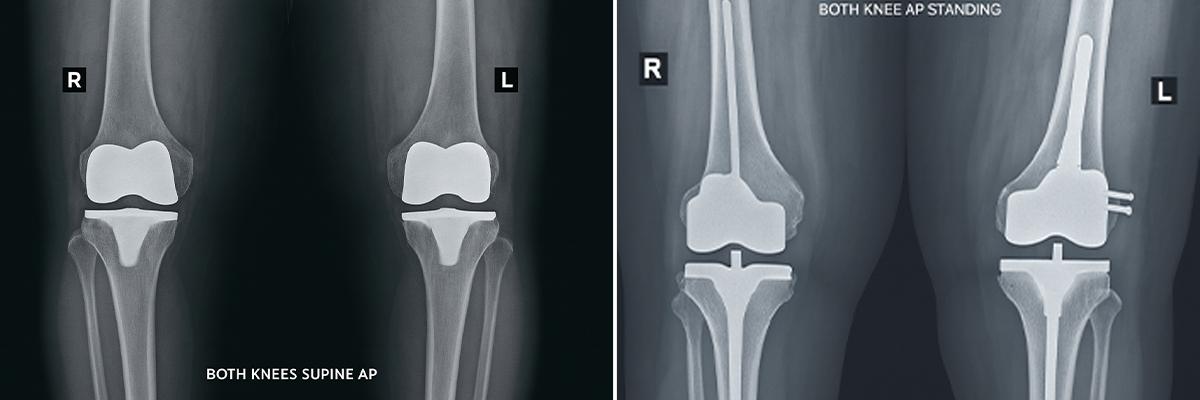

1. Removal and Replacement of the Old Implant

Revision knee replacement involves removing a previously implanted artificial knee joint and replacing it with a new, advanced implant to restore function and stability in the joint.

During revision surgery, some bone and ligament support may be compromised. Hence, Surgeons use more constrained implant designs that offer enhanced stability for weakened joints.